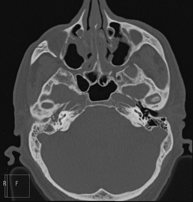

Prueba radiológica que consiste en obtener imágenes del macizo facial (cara) de alta definición anatómica mediante el empleo de un equipo de TC (Tomografía Computarizada). Indicaciones: tumores, cirugía plástica. - TC Oídos

Prueba radiológica que consiste en obtener imágenes del oído de alta definición anatómica (conducto auditivo interno y externo, tímpano, huesecillos del oído), mediante el empleo de un equipo de TC (Tomografía Computarizada). Indicaciones: trastornos de la audición, cuadros vertiginosos, mareos, acúfenos (pitidos). - TC Dental

Prueba radiológica que consiste en obtener imágenes de los huesos maxilares de alta definición anatómica (piezas dentarias, trayecto del nervio dentario), mediante el empleo de un equipo de TC (Tomografía Computarizada). Indicaciones: estudio previo a la extracción dental, estudio previo a implantes, tumores, absceso. - TC Senos paranasales

Prueba radiológica que consiste en obtener imágenes de los senos paranasales de alta definición anatómica, mediante el empleo de un equipo de TC (Tomografía Computarizada). Indicaciones: cefalea, tos crónica, mucosidad, infecciones faciales. - TC Peñascos

Prueba radiológica que consiste en obtener imágenes del hueso peñasco del temporal (oído interno, medio y externo) de alta definición anatómica mediante el empleo de un equipo de TC (Tomografía Computarizada). Indicaciones: pérdida de audición súbita o crónica, cuadros vertiginosos, mareo, malformaciones congénitas. - Angio – TC Troncos Supraaórticos